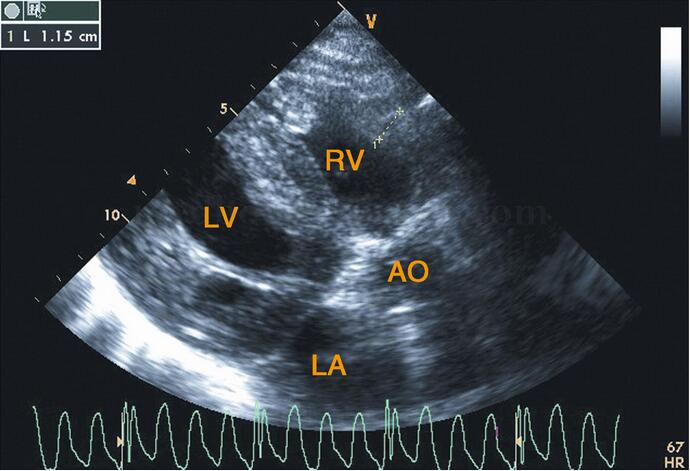

图2‐1‐213 心尖左室长轴切面前室间隔及左室后壁增厚,回声增强,并见颗粒样及团块状强回声

图2‐1‐214 左室长轴切面室间隔及左室后壁增厚,右室前壁增厚11.5mm

超声描述 双房扩大,左室心肌均匀对称性增厚(室间隔厚度19.8mm,后壁厚度20.0mm),右室前壁亦增厚11.5mm,心肌回声不均,可见颗粒状或小团块状强回声,室壁运动低平。心内膜、腱索、瓣膜及瓣环回声略增强,二尖瓣、主动脉瓣轻度反流,心包内可见少量无回声暗区。

超声诊断 双房扩大,双室均匀对称性肥厚,左室双期功能减低(考虑心脏淀粉样变可能性大)。二尖瓣、主动脉瓣轻度反流,少量心包积液。